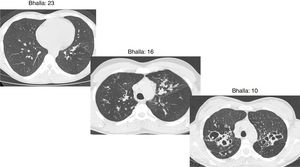

The final result obtained in the modified Bhalla score and in each of the items separately is shown by sex in Table 3. Those for which higher scores were recorded were extension of bronchiectasis, involvement of bronchial generations, and severity of bronchiectasis, thus illustrating practically generalized involvement of the bronchial tree. The modified Bhalla score was 13.70±3.87 points in women and 15.23±3.82 points in men (p=0.024). The items that showed greater involvement in women were sacculations, bronchial generations, and air trapping (Fig. 3).

CT images comparison between male and female with the same FEV1: (A) 35 year-old female. Severe bronchiectasis on upper lobes (scored 3), mild peribronchial thickening (scored 1), peripheral mucus plugs are present on upper lobes (scored 2), sacculations are present on left lower lobe. Sparing of distal peripheral zones is detected. Total Bhalla score: 10. FEV1 60%. (B) 40 year-old male. Moderate bronchiectasis (scored 2), mild peribronchial thickening (scored 1), mucus plugging (scored 2) was present on upper lobes. Sparing of distal peripheral zones is detected. Total Bhalla score: 17. FEV1 60%.